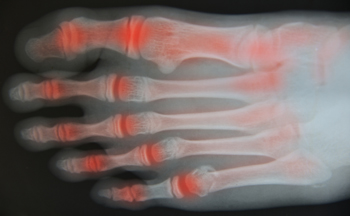

Rheumatoid arthritis is a chronic autoimmune condition where the immune system mistakenly attacks the joints, causing pain, stiffness, and swelling. The exact cause is not fully understood, but both genetic and environmental risk factors play a role. Family history may increase susceptibility, while environmental triggers such as smoking, infections, or exposure to certain substances can contribute to its development. Managing rheumatoid arthritis requires addressing both symptoms and overall joint health. A chiropractor can provide gentle adjustments to improve mobility, reduce discomfort, and support better alignment, which may ease strain on affected joints. If you have symptoms of rheumatoid arthritis, it is suggested that you consult a chiropractor who can provide natural, personalized relief.

Arthritis Relief

Arthritis, a common condition affecting millions, causes inflammation, stiffness, and pain in the joints. It can make everyday activities challenging and significantly impact quality of life. While there is no cure for arthritis, chiropractic care offers a natural, non-invasive way to manage symptoms and improve joint function.

Chiropractors focus on enhancing joint mobility and reducing inflammation through gentle, targeted adjustments. By realigning the body and restoring proper movement, chiropractic care can help relieve the pressure on arthritic joints, alleviating pain and stiffness. Adjustments also support better circulation, which may help reduce inflammation around affected joints.

In addition to adjustments, chiropractors often recommend specific exercises and stretches to strengthen muscles surrounding the joints, improving stability and reducing stress on the joints over time. They may also advise on lifestyle adjustments, such as dietary changes or ergonomic modifications, to support overall joint health.

Why Consider Chiropractic for Arthritis?

Chiropractic care provides a holistic approach to managing arthritis, addressing not just the symptoms but also underlying issues that contribute to discomfort. With regular care, many arthritis patients experience improved mobility, reduced pain, and a higher quality of life. Chiropractic care can be an effective complement to other arthritis treatments, supporting a more active, comfortable lifestyle.

What Types of Arthritis Can Benefit from Chiropractic Care?

Chiropractic care can benefit both osteoarthritis and rheumatoid arthritis by focusing on reducing joint strain and promoting better movement.